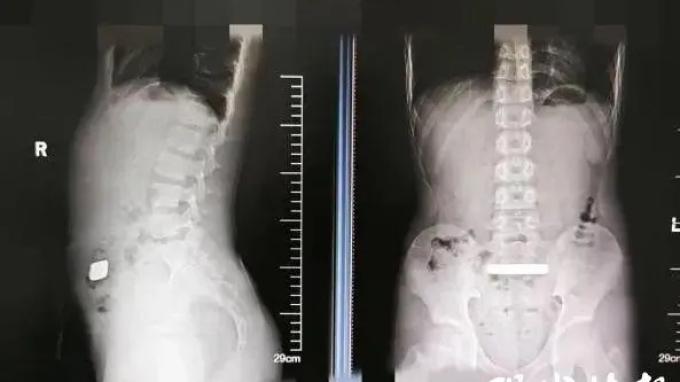

VIRAL DI CHINA - Tangkap layar pemberitaan dari Modern Express News (现代快报 - Xiandai Kuaibao) 8 April 2025, memperlihatkan hasil rontgen anak laki-laki yang menelan emas batangan. Anak 11 tahun itu awalnya mengeluh perutnya terasa kembung dan membengkak

Pemeriksaan sinar X mengungkapkan adanya benda logam berdensitas tinggi yang tersangkut di saluran usus anak laki-laki itu.